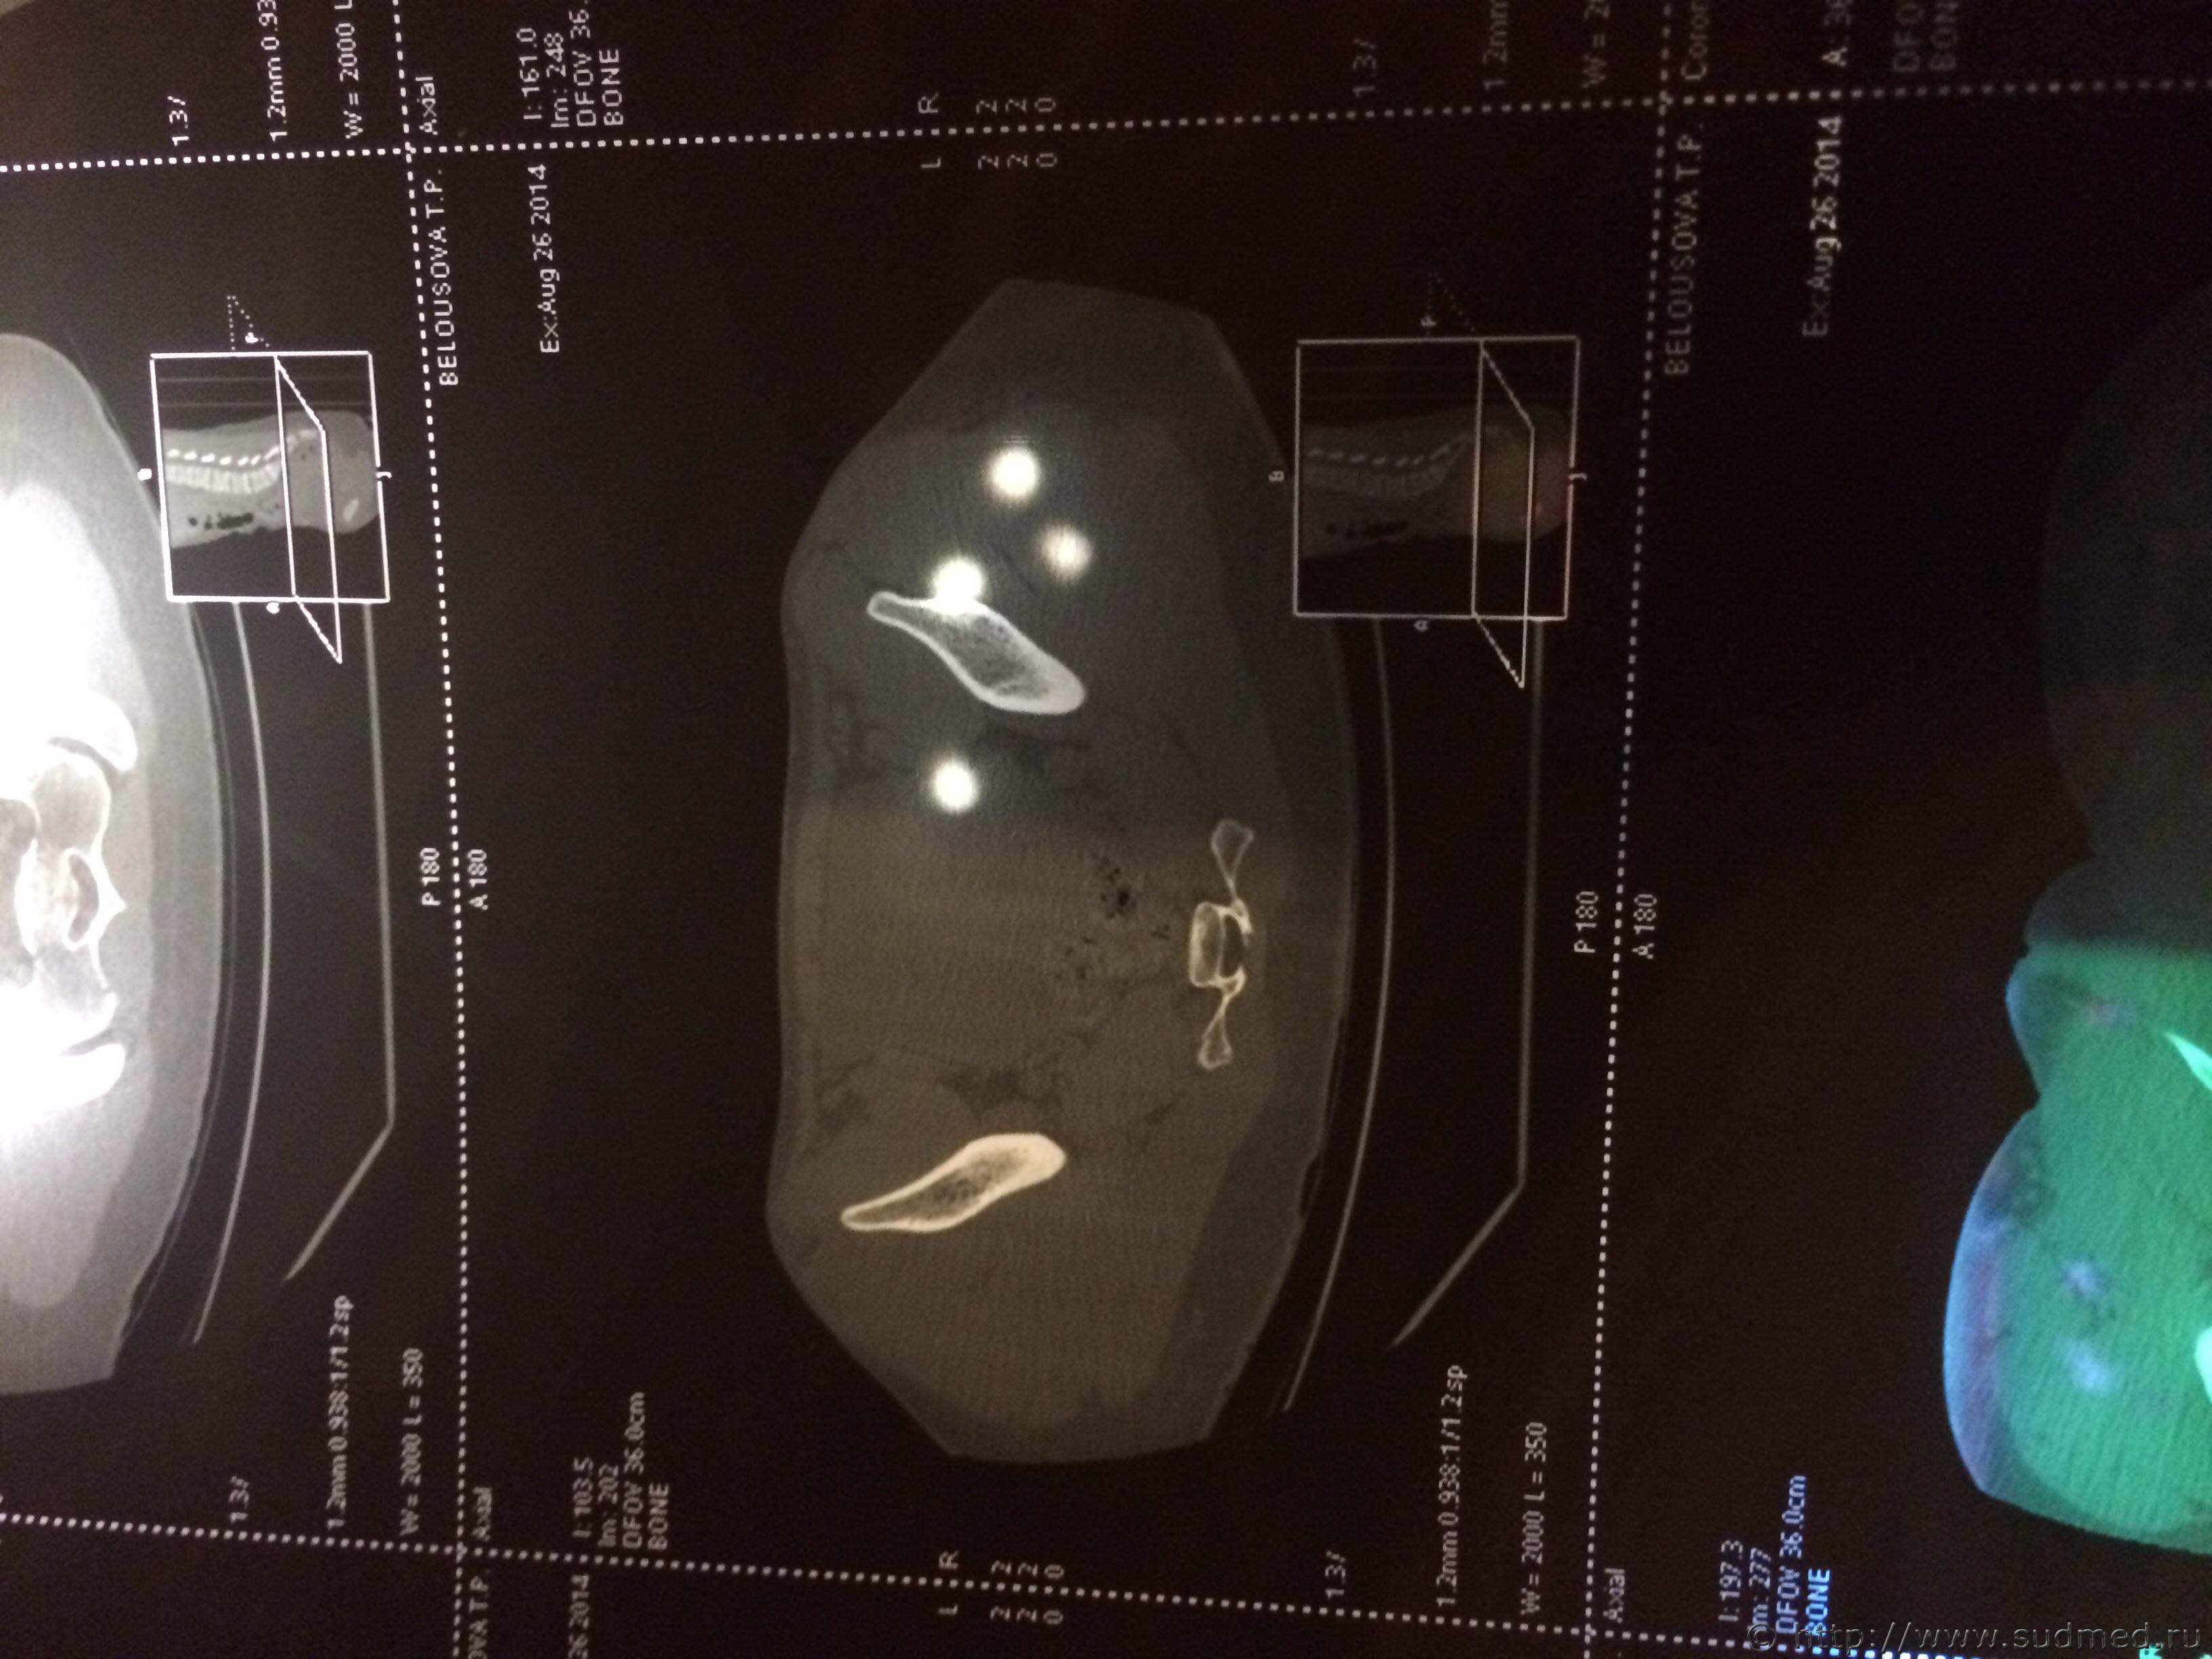

Спасибо! У меня результаты КТ, ошиблась)

КТ

Как мне видится - вертикальный перелом крестца. Тяжкий вред.

Впрочем, оставляю небольшую вероятность, что я не видел все сканы, да и качество их здесь, разумеется, хуже, чем изображение на пленке или на экране компьютера у врача, работающего на томографе.